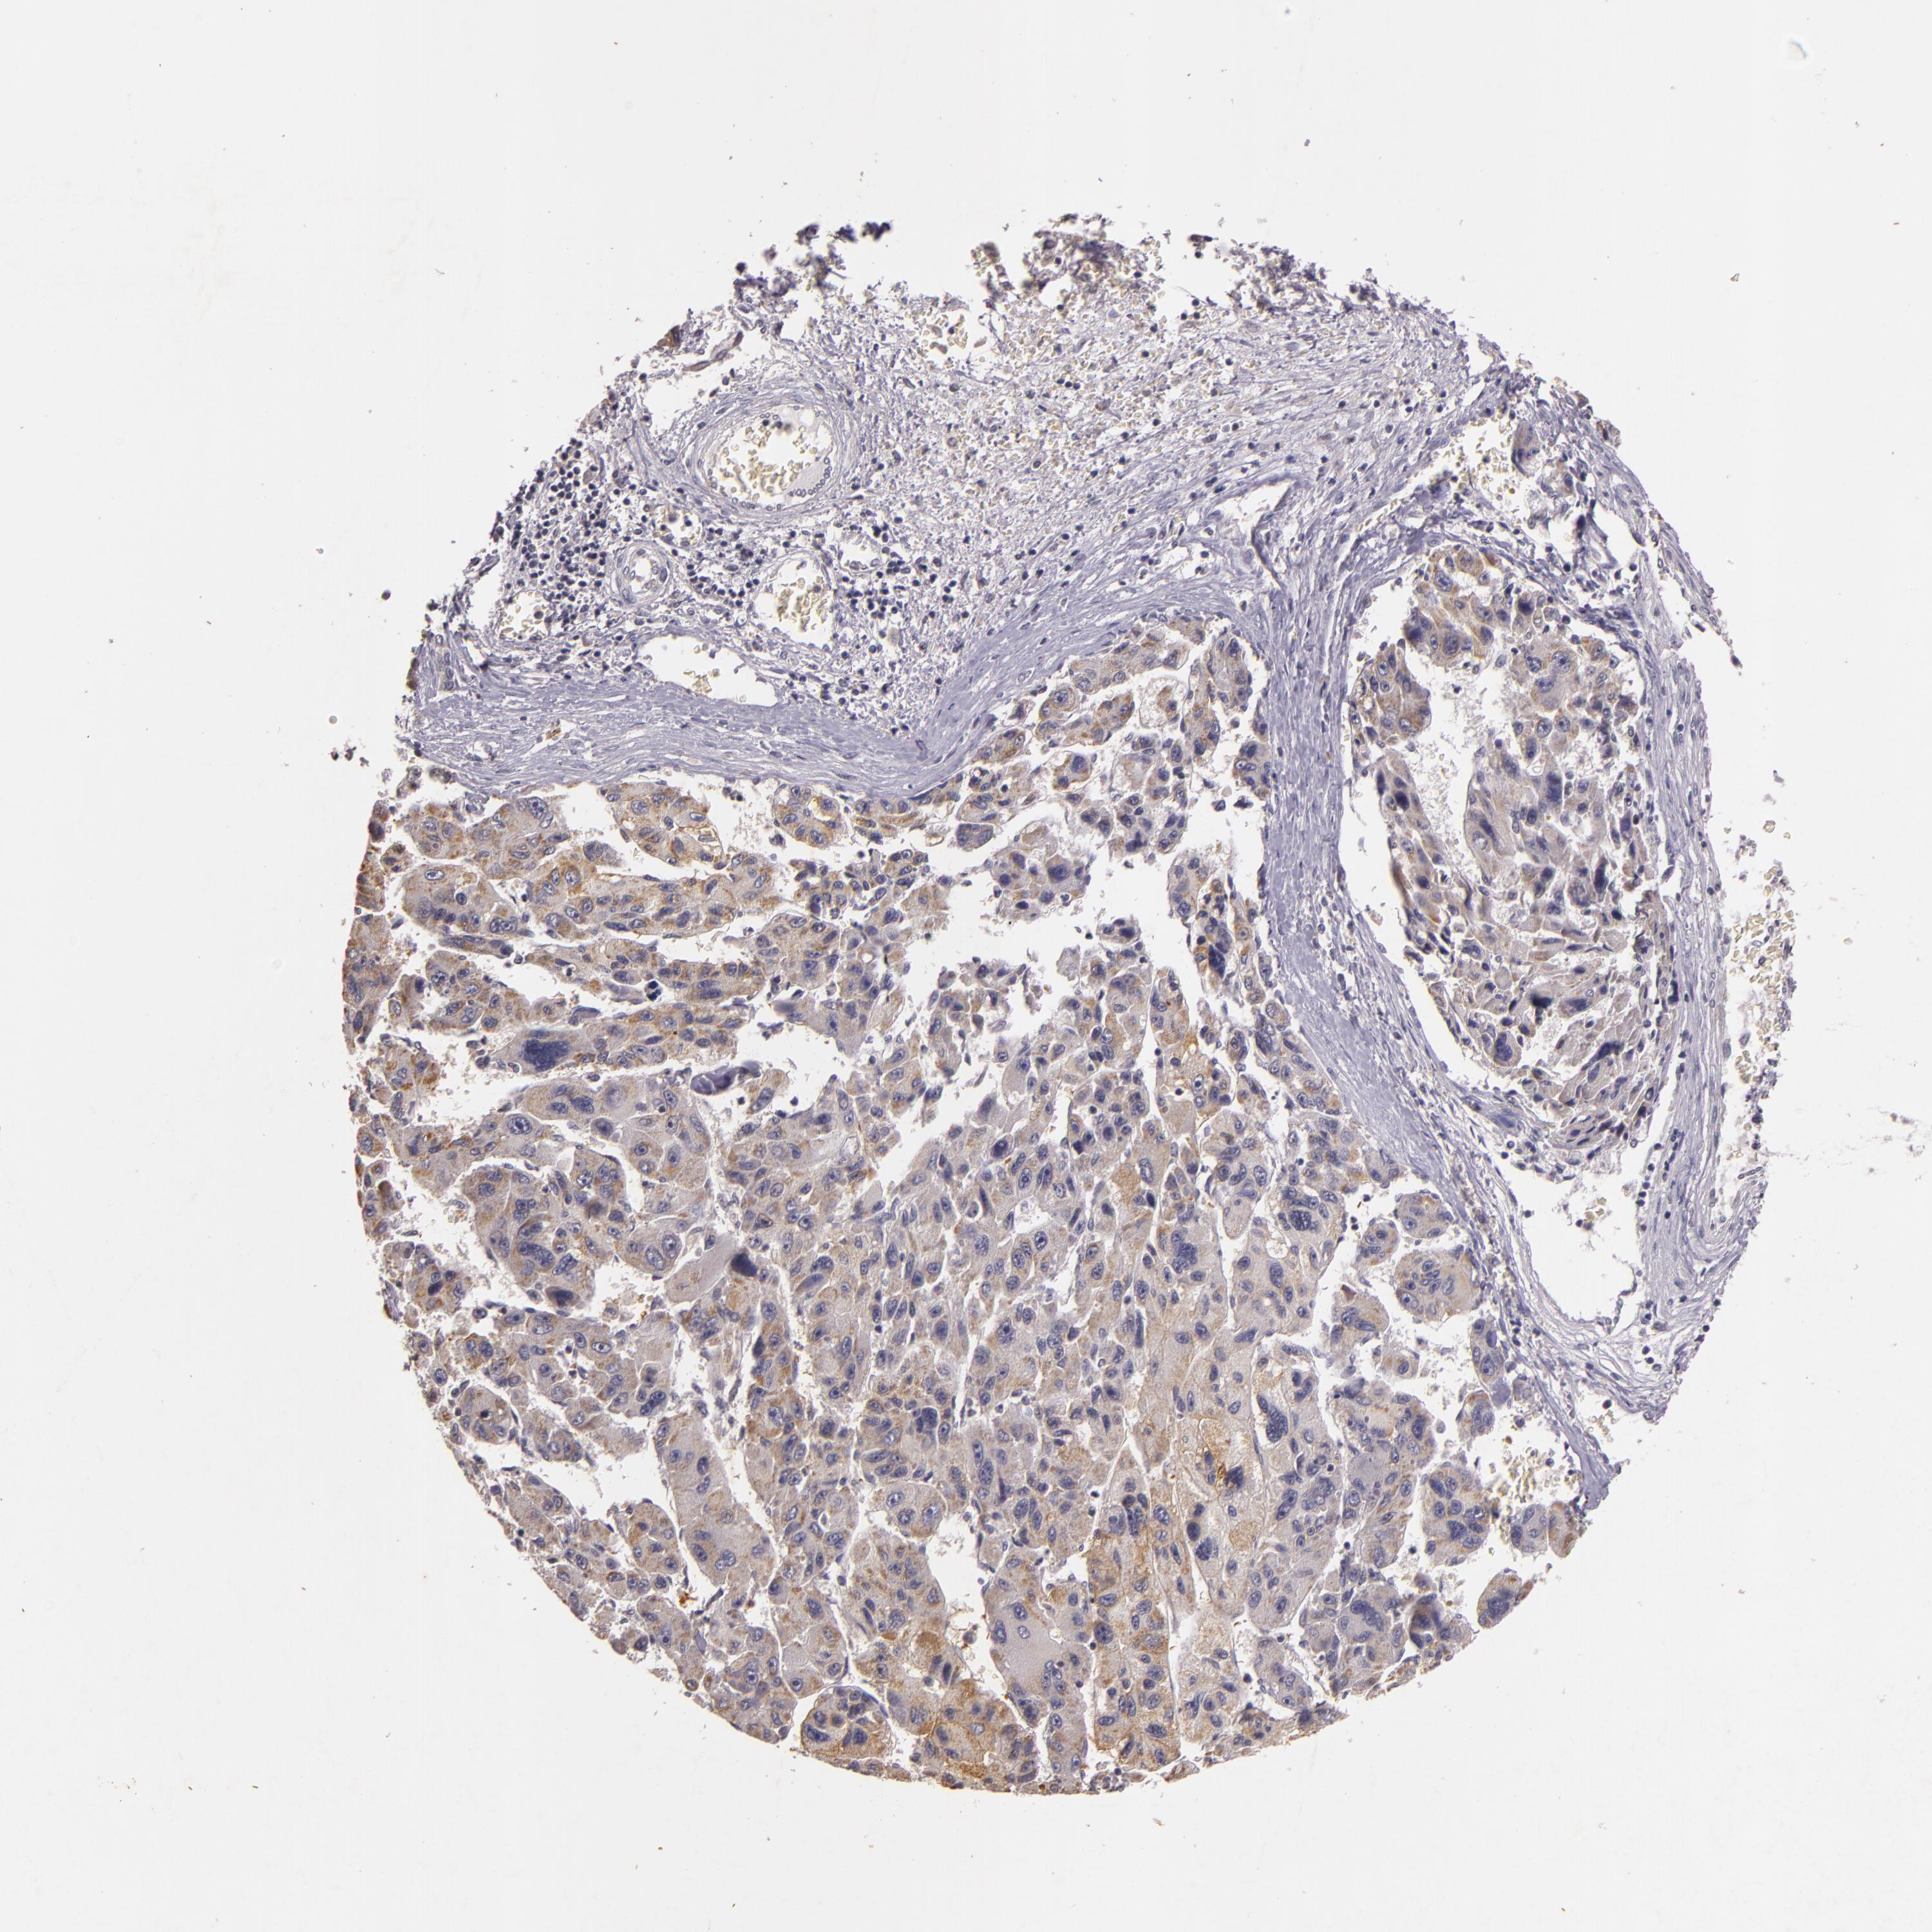

LIVER CANCER - Protein expressioni

A mouse-over function shows sample information and annotation data. Click on an image to view it in a full screen mode. Samples can be filtered based on level of antibody staining by selecting one or several of the following categories: high, medium, low and not detected. The assay and annotation is described here.

Note that samples used for immunohistochemistry by the Human Protein Atlas do not correspond to samples in the TCGA dataset.

Antibody stainingi

Antibody staining in the annotated cell types in the current human tissue is reported as not detected, low, medium, or high, based on conventional immunohistochemistry profiling in selected tissues. This score is based on the combination of the staining intensity and fraction of stained cells.

Each image is clickable and will lead to virtual microscopy that enables deeper exploration of all samples and also displays staining intensity scores, fraction scores and subcellular localization as well as patient and tissue information for each sample.

Antibody HPA003425

Antibody CAB002170

Staining

High

Medium

Low

Not detected

Intensity

Strong

Moderate

Weak

Negative

Quantity

>75%

75%-25%

<25%

None

Location

Nuclear

Cytoplasmic/membranous

Cytoplasmic/membranous,nuclear

Carcinoma, Hepatocellular, NOS

Cholangiocarcinoma